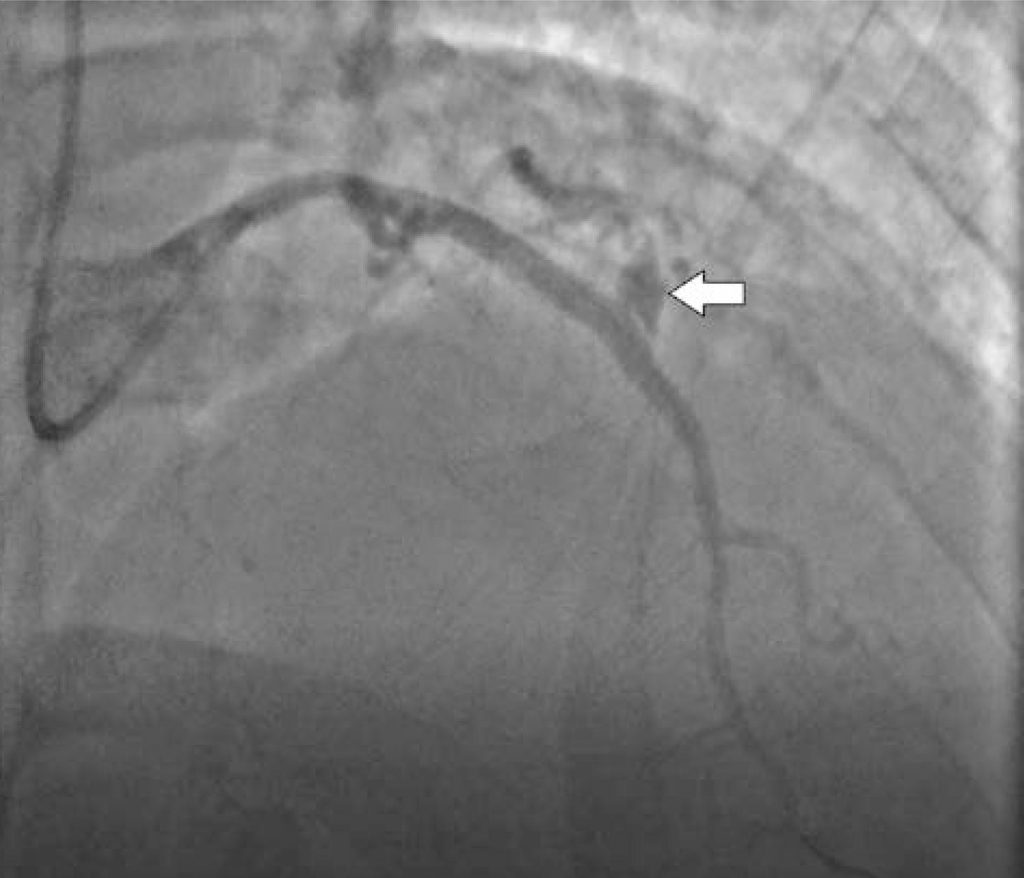

Figure 2

In-stent left anterior descending type III perforation (white arrow), with frank pericardial drainage.